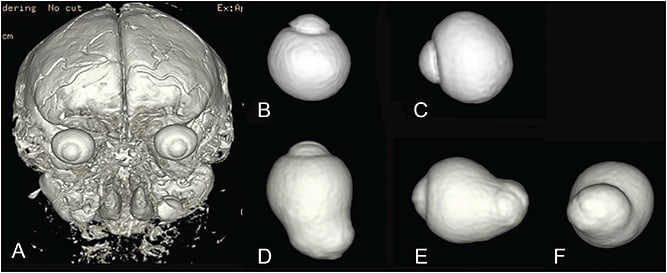

To overcome these problems, Moriyama and the author4,7,8 established a new technique called 3D MRI to analyze the entire shape of the eye (Figure 4). The 3D MRI technique is well suited to examine the eye shape over a wide area that can encompass even a large posterior staphyloma from any angle. The author used 3D MRI and reported posterior outpouching of the globe, suggesting staphyloma was observed in 50.5% of the eyes with mean axial length of 30.0 mm.4 More recently, the author used a combination of 3D MRI and Optos in Japanese and Spanish patients and reported a similar prevalence (55% of the eyes with mean axial length of 30.5 mm).9 These data also showed that even among very long eyes (axial length of 30 mm) about a half of them do not have posterior staphylomas; they were simply elongated in an anteroposterior direction.9

The most predominant type was wide macular staphyloma (74% of eyes with staphyloma), followed by narrow macular staphyloma (15% of eyes with staphyloma).

To overcome these issues with Curtin’s classification, the author4 determined the type of staphylomas based on the shape of the entire eye using scans by 3D MRI. To simplify Curtin’s classification, the author analyzed only the contour of the outermost border of staphylomas. This resulted in Curtin types VI to X being placed into the type I category. The staphyloma type is renamed according to its location and distribution; this facilitates with memorization. (Figure 7).